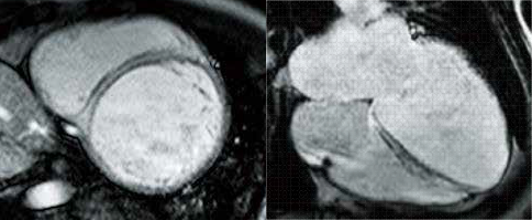

Клінічний випадок 2

Історія пацієнта

У 43-річної жінки була множинна мієлома та задокументовані відкладення амілоїду в шкірі та дванадцятипалій кишці. На ехокардіографії виявлено порушення функції лівого шлуночка (ЛШ). Її направили до нашого центру візуалізації з підозрою на амілоїдоз серця.

Cine MRI

LGE

Кіно МРТ виявила гіпертрофію ЛШ та дифузний гіпокінез.

Пізнє посилення гадолінію показало дифузне та трансмуральний гіперсигнал в ЛШ, що вказує на дифузні амілоїдні відкладення.